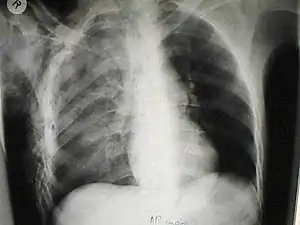

Pulmonary laceration may not be visible using chest X-ray because an associated pulmonary contusion or hemorrhage may mask it.[1][9] As the lung contusion clears (usually within two to four days), lacerations begin to become visible on chest X-ray.[3] CT scanning is more sensitive and better at detecting pulmonary laceration than X-rays are,[1][5][12][15] and often reveals multiple lacerations in cases where chest X-ray showed only a contusion.[12] Before CT scanning was widely available, pulmonary laceration was considered unusual because it was not common to find with X-ray alone.[12] On a CT scan, pulmonary lacerations show up in a contused area of the lung,[9] typically appearing as cavities filled with air or fluid[16] that usually have a round or ovoid shape due to the lung's elasticity.[4]

Hematomas appear on chest radiographs as smooth masses that are round or ovoid in shape.[1] Like lacerations, hematomas may initially be hidden on X-ray by lung contusions, but they become more apparent as the contusion begins to heal.[1] Pneumatoceles have a similar shape to that of hematomas but have thin, smooth walls.[17] Lacerations may be filled completely with blood, completely with air, or partially with both.[4] Lacerations filled with both blood and air display a distinctive air-fluid level.[4] A single laceration may occur by itself, or many may be present, creating an appearance like Swiss cheese in the radiography of the lung.[4]